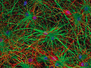

In 1st Place Hassanain Qambari & Jayden Dickson of The Lions Eye Institute Department of Physiology & Pharmacology, Perth, Western Australia, Australia with their image of a rodent optic nerve head showing astrocytes (yellow), contractile proteins (red) and retinal vasculature (green) made using confocal fluorescence microscopy 20X objective lens magnification with image stacking